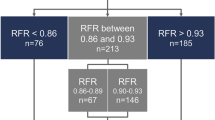

Compared with the iFR, the index value of the ICE-T was lower, the flow velocity was higher, and the intracoronary resistance was lower in all conditions where different coronary arteries were measured with or without hyperemia. The ADVISE study reported that the classification agreement (accuracy) between the iFR and the FFR was 94%; however, around the cut-off point for ischemic diagnosis, the iFR-FFR concordance rate was < 50%30. Our previous study findings indicated that the ICE-T is better than the iFR in terms of agreement with an ischemic diagnosis according to the FFR, although that study had a small sample size. In particular, the ICE-T had a higher concordance rate with the FFR for the diagnosis of ischemia in borderline cases such as the iFR adenosine zone (0.86 ≤ iFR ≤ 0.93; accuracy, overall; ICE-T 90%, iFR, 72.5%; adenosine zone; iFR 65%, ICE-T 80.0%)21. The usefulness of the IC-ECG in predicting microvascular obstruction in myocardial infarction31 and post-procedural myocardial injury in angina pectoris has also been reported32. These reports indicate that the local myocardial condition can be assessed sensitively using the IC-ECG. The combined use of pressure wire and the IC-ECG to assess myocardial ischemia and myocardial viability simultaneously may reduce the cost of cardiac magnetic resonance imaging and stress myocardial scintigraphy. The ICE-T requires a shorter analysis period than the iFR because it can selectively detect finer electrical potentials representing cardiac muscle activity near the tip of the pressure wire where the pressure sensor is located33. Therefore, the ICE-T measure might select an analysis interval with lower intracoronary resistance than the aortic pressure-dependent iFR measure regardless of the measurement conditions.